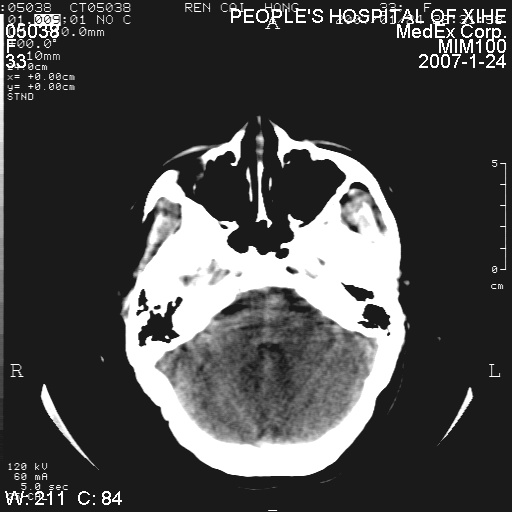

以下是引用卜一在2007-1-25 6:40:00的发言:[br]左侧额叶囊实混杂性病灶,多考虑胶质细胞瘤(ⅱ-ⅲ级),建议增强检查。[br]支持!

以下是引用守望可可西里在2007-1-25 0:13:00的发言:[br]左侧额叶囊实混杂性病灶,多考虑胶质细胞瘤(ⅱ-ⅲ级),建议增强检查!